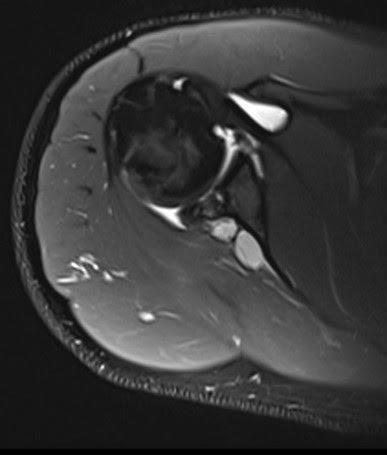

Se identifica un quiste paralabral lobulado de 3.4 x 2.3 cm en la escotadura espinoglenoidea, sin comunicación aparente con la articulación glenohumeral.

Se observa una rotura basal incompleta del labrum glenoideo tipo SLAP VIII, que se extiende de las 7 a las 3 en sentido horario, lo cual probablemente generó el quiste.

Figura 2: Secuencia axial PD-FS: quiste bilobulado en la escotadura espinoglenoidea.

Se trata de un caso de quiste paralabral posterior en la escotadura espinoglenoidea, secundario a una rotura labral basal, sin comunicación con la cápsula articular y con signos incipientes de denervación del músculo infraespinoso, lo cual sugiere compresión extrínseca del nervio supraescapular.